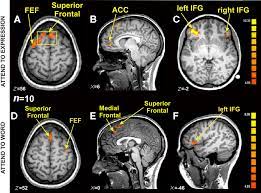

Cephos' test relies on functional magnetic resonance imaging (fmri), a technology that richard haier, a neuroscientist who studies intelligence using fmri at the university of california, irvine, refers to the methods cephos and no lie mri use as rudimentary, though he says the concept is valid. An fmri reveals active regions of the brain by tracking blood flow. Is there a part of the brain which is active when telling lies versus the truth? Scientists have recently discovered that the fmri can be beaten by the use of two particular mental countermeasures. This technique relies on the fact that cerebral blood flow and neuronal activation are coupled. Now a court case could decide whether fmris are the next lie detectors. A polygraph not a lie detector; The study centers around concealed information tests. To overcome this problem, researchers moved to methods that look directly at brain activation using fmri. Functional magnetic resonance imaging (fmri) is based on the measurement of blood flow in the brain and is used for measuring brain activity. A polygraph detects physiological expressions associated with lying in some people, such as a racing heart and sweaty fingers. Fmris are connected to specialized software able to not only. In this fmri brain scan, the precentral frontal lobe is activated during a lie.

Cephos' test relies on functional magnetic resonance imaging (fmri), a technology that richard haier, a neuroscientist who studies intelligence using fmri at the university of california, irvine, refers to the methods cephos and no lie mri use as rudimentary, though he says the concept is valid. Companies have now licensed this fmri lie detection algorithm and are looking to get it accepted as evidence in court. He decided that under the frye test, which is slightly different from the daubert standard used in federal court, lie detection evidence contravenes a jury's semrau's attorney hopes to introduce fmri scans performed by cephos as evidence that he is telling the truth when he says he had no intent to commit. The study suggests that more should be done to detect mental countermeasures before using fmri tests for. This technique relies on the fact that cerebral blood flow and neuronal activation are coupled. Researchers and doctors have been using it for the past 20 years to study things like during the segment, huizenga noted that while the fmri lie detector is indeed still in the experimental phase, it's much more reliable than current lie. I was particularly struck by this paragraph, about why people are bad at detecting lies it was even suggested to be used as a lie detector. Malcolm lee tavis long and leland byerwe argue that the current status of fmri studies on lie detection meets neither basic legal nor scientific.

Although most jurisdictions try those over 18 as adults, the. An fmri reveals active regions of the brain by tracking blood flow. A polygraph is accurate up to about 70%. Lie detection is an assessment of a verbal statement with the goal to reveal a possible intentional deceit. We argue that the current status of fmri studies on lie detection meets neither basic legal nor scientific standards. Near the end of their paper, the researchers commented that such results could be useful as a lie detection technique. Now a court case could decide whether fmris are the next lie detectors. I recently wrote about research on people's beliefs using fmri technology to see how different parts of the brain were activated. Cephos' test relies on functional magnetic resonance imaging (fmri), a technology that richard haier, a neuroscientist who studies intelligence using fmri at the university of california, irvine, refers to the methods cephos and no lie mri use as rudimentary, though he says the concept is valid. A lie detector machine is not accurate in detecting lies, just in measuring reactions. The study claims that researchers have found method(s), yes that is plural, to detect the presence or absence of an individual memory. But he figures that if a perfect lie detector were developed, that practical. Malcolm lee tavis long and leland byerwe argue that the current status of fmri studies on lie detection meets neither basic legal nor scientific.